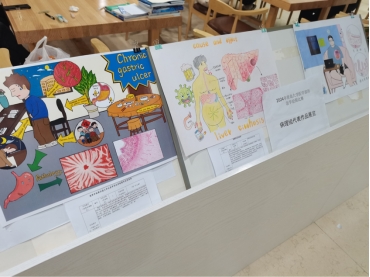

第四届病理学绘图大赛,选拔优秀绘图作品参加全国“高等医学院校第三届大学生形态学绘图作品评选”(3-病理学组),并在5月20日到5月28日之间进行了优秀病理绘图作品的展示。活动宗旨是继续以“学”为中心,以“教”为主导,注重学生“知识、能力和素质”培养,尤其注重想象力、创新思维能力、综合素质的培养,激发学生学习兴趣,将美育融入课堂,推动和促进医学本科教学质量提升。展览活动共展示了病理学呼吸系统及消化系统疾病的18副病理绘图作品,绘图的学生主要是2021级医学部各专业的本科生,保护手绘作品及电子绘图作品。此次画展得到了医学部、男同性恋av

病理学组获得一等奖作品照片

病理学组获得一等奖作品照片

病理学组获得一等奖作品照片

病理学组获得一等奖作品照片

病理学组获得一等奖作品照片

病理学组获得一等奖作品照片